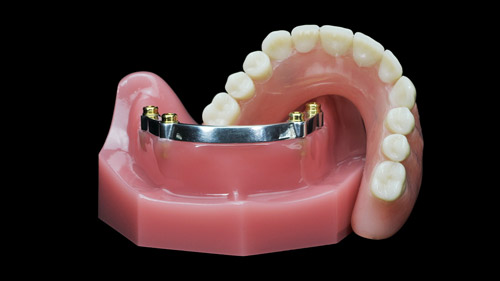

In the Restorative Phase, the implants are rehabilitated to place the bridges. Each bridge will be permanently supported and secured by 2 implants on each side.

You will receive 3 Zirconia or Porcelain Bridges, these materials make bridges lighter and up to fifty percent more fracture-resistant, giving our patients more durable dental restorations.